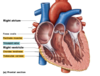

What do the tricuspid and mitral valves separate?

- tricuspid = right atrium and ventricle

- mitral = left atrium and ventricle

When looking at the heart anteriorly, out of the pulmonary veins supplying oxygenated blood from the lungs to the heart, and the pulmonary arteries carrying de-oxygenated blood from the heart to the lungs, which is superior and inferior?

- pulmonary arteries are superior

- pulmonary veins are inferior

What is the sinoatrial node of the heart?

- specialised cardiac muscle

- located in upper wall of atrium

- junction of superior vena cava

- pacemaker of the heart